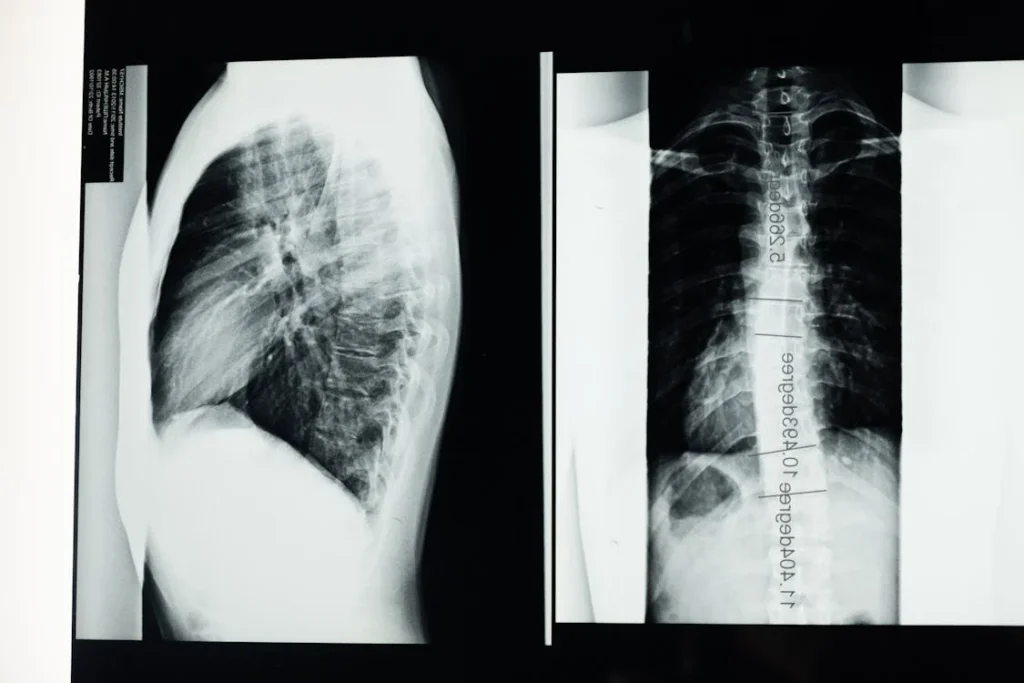

A gerincferdülés, vagyis scoliosis egy igen gyakori mozgásszervi elváltozás, amely során a gerincoszlop oldalirányban elhajlik. A probléma sokszor már gyermekkorban vagy serdülőkorban jelentkezik, de felnőtteknél is kialakulhat. A gerincferdülés tünetei széles skálán mozognak, és súlyosságuktól függően változhat a mindennapi életre gyakorolt hatásuk. A következő cikkben részletesen bemutatjuk a gerincferdülés főbb tüneteit, és azt, hogy miért fontos a korai felismerés.

A gerincferdülés egyik legszembetűnőbb tünete az aszimmetrikus testtartás. A gerinc oldalirányú elhajlása miatt a test egyik oldala magasabban helyezkedik el, mint a másik. Ez leginkább a vállak és a csípő vonalában vehető észre: az egyik váll magasabban állhat, míg a másik lejjebb süllyedhet.

Az aszimmetrikus testtartást gyakran kíséri a bordák elmozdulása is. A gerincferdülés következtében a bordák elcsavarodhatnak, ami a hát egyik oldalán domborulatot, míg a másik oldalon süppedést okozhat. Ez különösen előre hajolva válik feltűnővé, amikor a hát egyik oldala magasabban áll, mint a másik.

A gerincferdülés súlyosabb eseteiben a mellkas deformitása is előfordulhat, ami légzési nehézségeket okozhat. A gerincoszlop elhajlása a bordák elmozdulásához vezethet, ami befolyásolhatja a tüdő kapacitását és működését. Ez különösen igaz, ha a ferdülés a háti (thoracalis) gerincszakaszt érinti, mivel ez a rész kapcsolódik közvetlenül a mellkashoz.